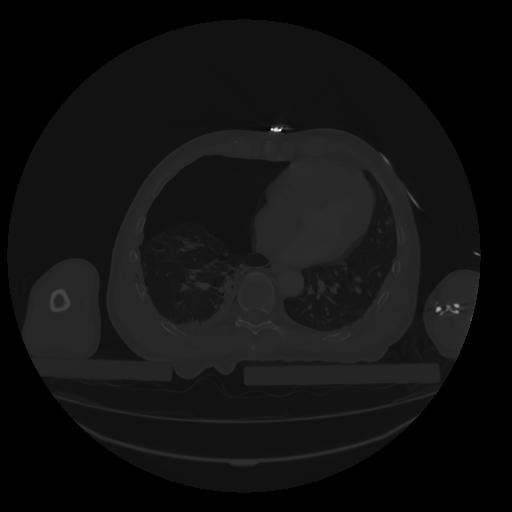

28 CUERPO,CE,Vol,2.0,CUERPO,,